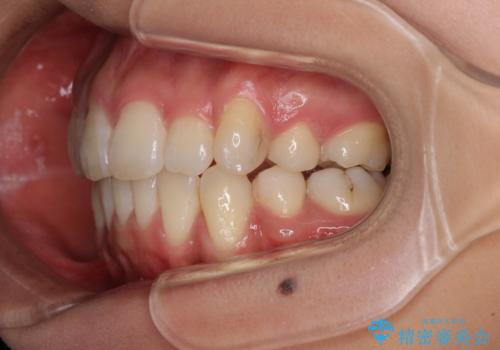

- 以前の矯正治療の後戻りにより、上下の前歯がでこぼこになってしまったことを気にして来院された患者様です。

口元がこれ以上突出することなく前歯の叢生が改善できるよう、歯と歯の間を削ってスペースを獲得し、インビザラインを用いて整えていくこととしました。

目安の装着時間である1日22時間をしっかりと実践してくださり、半年強という短期間で治療を終えることができました。